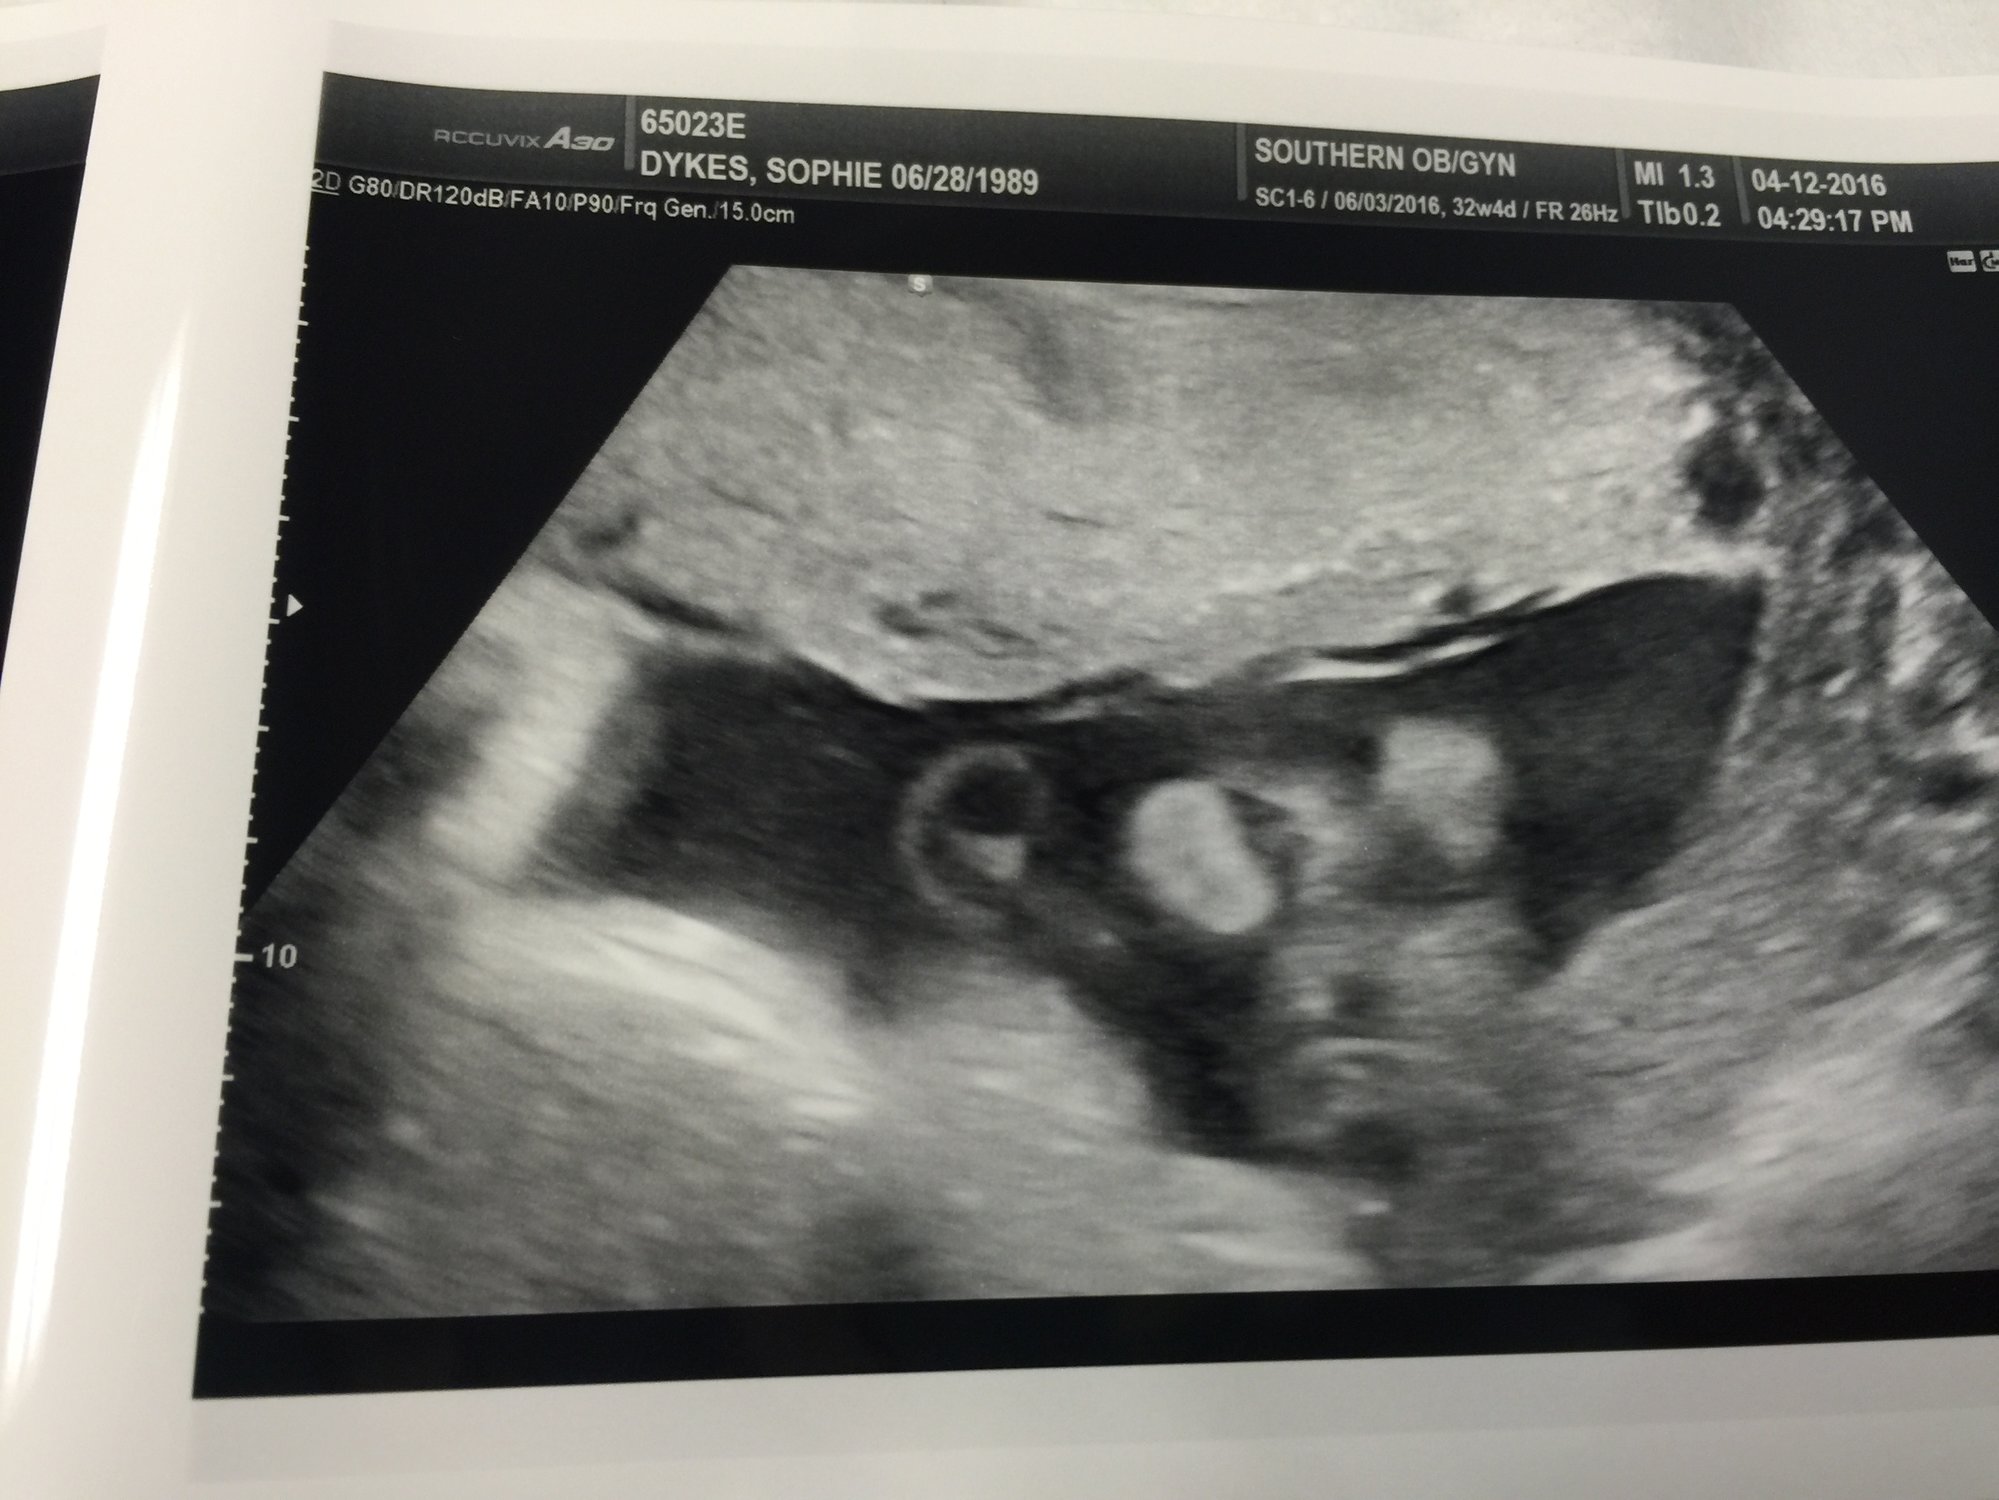

• @VikingGirl12 that picture is so cute (once I figure out what I was looking at).  Glad she's doing so well!  Also, just an FYI, your name and birthday are visible on the sonogram, internet stranger danger and all.

• @VikingGirl12 SOOOOOOO happy to hear she's doing well!!! Stay in there little girl :)

• @VikingGirl12. She is so adorable. Glad she is staying in there longer.

@VikingGirl12 adorable update! She sounds so sweet. Boo for GD, but at least it's not too much longer.

I had my first of many bpp's today and she made a perfect score so no baby today! Baby girl is 4lb8oz at 32+5 so she's big like her brother! The fluid on her kidneys was immeasurable which is so good. We found a new Down syndrome marker, but it's a super cute one! Tongue thrusts!

Aaaaand, they're treating me for gestational diabetes so I start my twice a day finger pricks tomorrow. Boo!